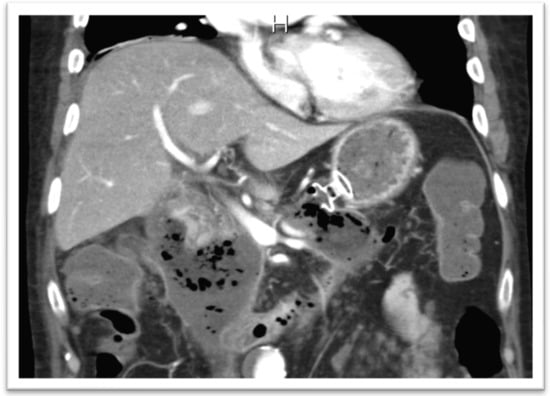

In the setting of malignant GOO, several randomized trials have compared the outcomes of surgical gastrojejunostomy (SGJ), endoscopic SEMS placement (Figure 11), and EUS-GEA anastomosis (Figure 12) [2,13,14,15,16,17]. The main limitation of SGJ is commonly considered its invasiveness, associated with the occurrence of post-surgical adverse events, as with gastroparesis and post-operative infections [2,13].

The authors of the SUSTENT study, comparing endoscopic SEMS placement and SGJ, despite slow initial symptom improvement, suggested that SGJ was associated with better long-term results and is therefore the treatment of choice for patients with a life expectancy of 2 months or longer. Because stent placement was associated with better short-term outcomes, they considered this treatment preferable for patients expected to live less than 2 months [2,18].

A recent meta-analysis about published data on EUS-GEA including twelve studies (290 patients) showed that malignant GOO was the main procedure indication, with the direct puncture technique the most frequently adopted technique. Pooled technical success and clinical success were 93.5% and 90.1%, respectively, with a pooled total AEs rate of 11.7%, mainly mild/moderate [2,19].